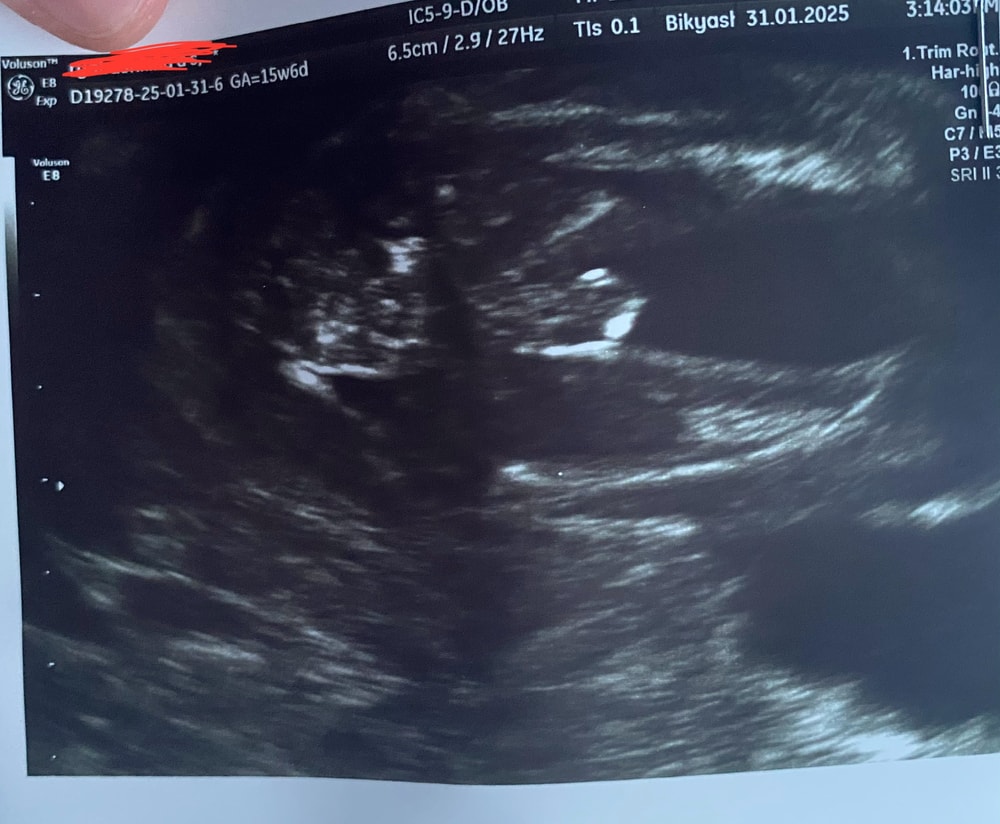

Пол малышаВсем привет! Очень волнует вопрос, какого же пола малыш) На фото 16 недель и 5 дней, была платно у врача она показала прям вот нашего мальчика. В ЖК сказали что кажется девочка, но толком не посмотрели, смотрели только длину матки.

Мальчик) у нас в 15,6 уже видно было, но нам прям увеличили фото, что было проще понять